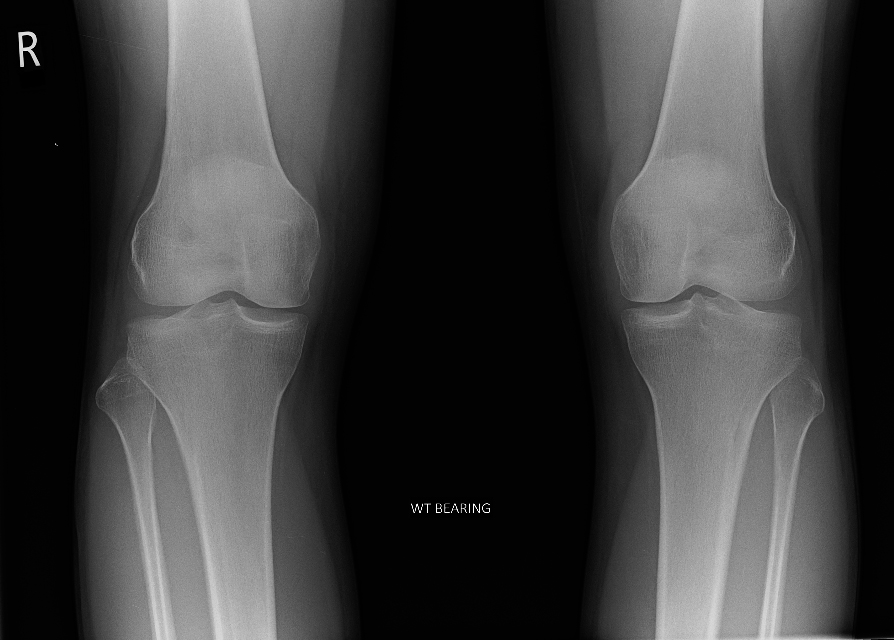

| 7 |

Abnormal fr tibia |

Abnormal Right tibial intercondylar fracture |

Correct |